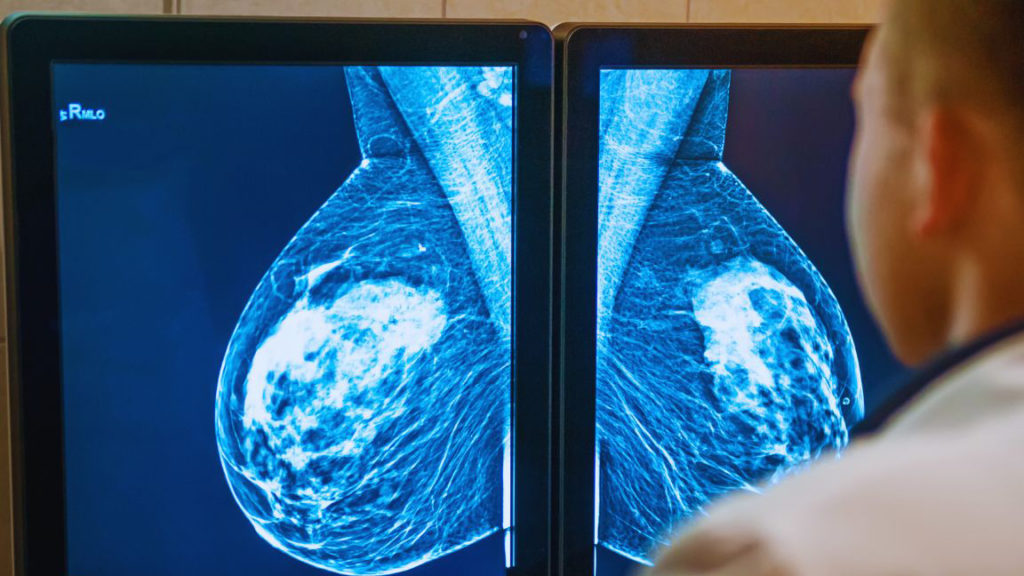

У череповчанки благодаря диспансеризации обнаружили рак груди на ранней стадии

Туда обратилась женщина с уплотнением в груди. После маммографии в рамках диспансеризации ее направили к онкологу, который сразу назначил УЗИ и биопсию. Результаты подтвердили, что нужна операция. После нее она восстановилась и теперь под постоянным наблюдением врачей, сообщили в пресс-службе правительства области.

Рак обнаружили на первой стадии, и своевременное лечение спасло жизнь. Пациентка Череповецкой городской поликлиники №7 дала совет женщинам с подобным диагнозом: